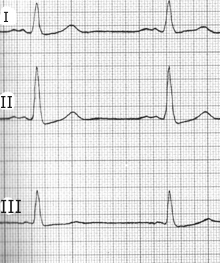

Die Höhe von P ist mit ca. 0,2 noch normal,

in Abl. I und II ist P jedoch deutlich verbreitert

(ca. 0,15 sec),

der zweite Anteil deutet auf eine Störung im linken Vorhof hin.

P sinistro-atriale